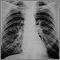

Exams and Tests

Tests to confirm the diagnosis and rule out similar diseases include:

People with silicosis are at high risk for developing tuberculosis (TB). Silica is believed to interfere with the body's immune response to the bacteria that cause TB. People with silicosis should have skin tests to check for exposure to TB. Those with a positive skin test should be treated with anti-TB drugs. Any change in the appearance of the chest x-ray may be a sign of TB.